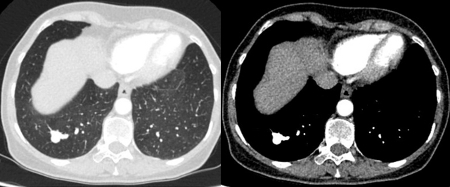

The remaining causes are infrequent and include mucoid impaction, septic emboli, arteriovenous malformations, and pulmonary amyloidosis.

[Figure caption and citation for the preceding image starts]: Computed tomography (CT) showing two left lower lobe peripheral nodules (one slightly spiculated and the other with smoother margins) in a patient presenting with fever, high inflammatory serum markers, and blood cultures confirming Streptococcus intermedius. Both nodules completely resolved following a course of linezolid, consistent with septic emboliFrom the collection of Dr George Tsaknis, MD, PhD, FRCP(London), MRQA, MAcadMEd, PGCert; used with permission [Citation ends].